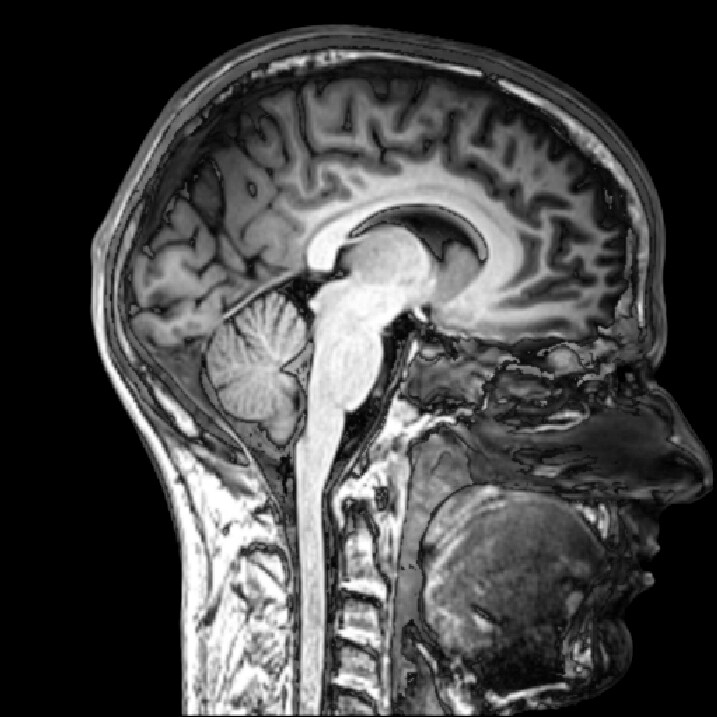

Why is a biobank required to research TBI? Long term effects of TBI are believed to be related to chronic traumatic encephalophathy (CTE), a progressive neurodegenerative disorder eventually leading to brain cell death. Currently, CTE can only be diagnosed postmortem through examination of brain tissue. Recent research has shown CTE can be caused by a single exposure to a blast, so the disorder is of particular interest to the DoD.

What are the goals of the biobank and research effort? The brain tissue repository will support CNRM’s research into TBI. CNRM is developing improved ways to diagnose TBI, models of the brain after an injury and programs to improve rehabilitation.

How will the brains be studied? Brain tissue will be analyzed along with clinical information about the donor, such as the intensity and number of blasts the soldier was exposed to and the symptoms they experienced later in life.